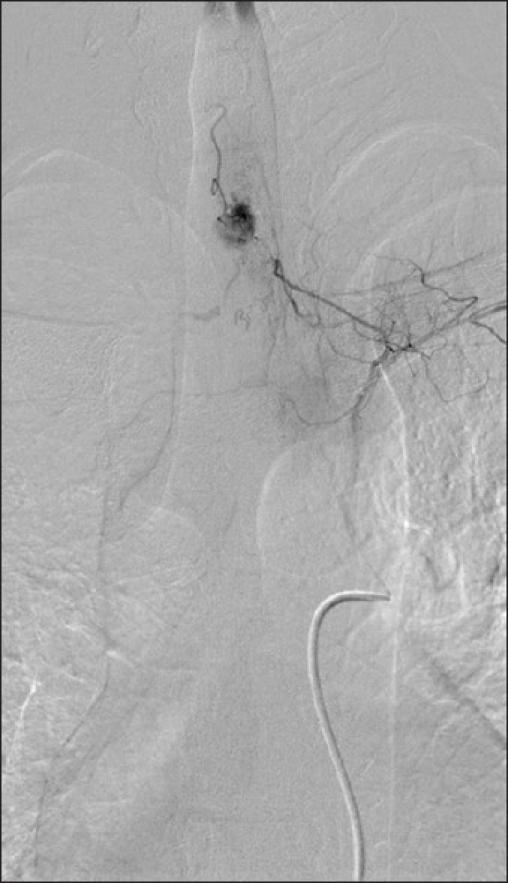

Seventeen patients underwent microsurgical resection of 20 spinal HBs at the Department of Neurosurgery at Helsinki University Central Hospital (HUCH). Thirteen tumors were in the cervical spine, five in thoracic and one patient had two lumbar lesions. MRI tumor showed an associated syrinx in 16 patients (94%). Tumor volume ranged from 27 to 2730 mm(3). Out of 17 patients, 11 (65%) tested positive for VHL in mutation analysis. Five of these patients with tumors ranging from 55 to 720 mm(3) were treated prophylactically.

17例患者在赫尔辛基大学中心医院(HUCH)神经外科接受了20例脊髓HB的显微手术切除。13个肿瘤位于颈椎,5个位于胸椎,1例患者有2个腰椎病变。MRI检查显示16例患者(94%)伴有脊髓空洞症。肿瘤体积为27至2730立方毫米。在17例患者中,11例(65%)在突变分析中VHL检测呈阳性。其中5例肿瘤体积为55至720立方毫米的患者接受了预防性治疗。